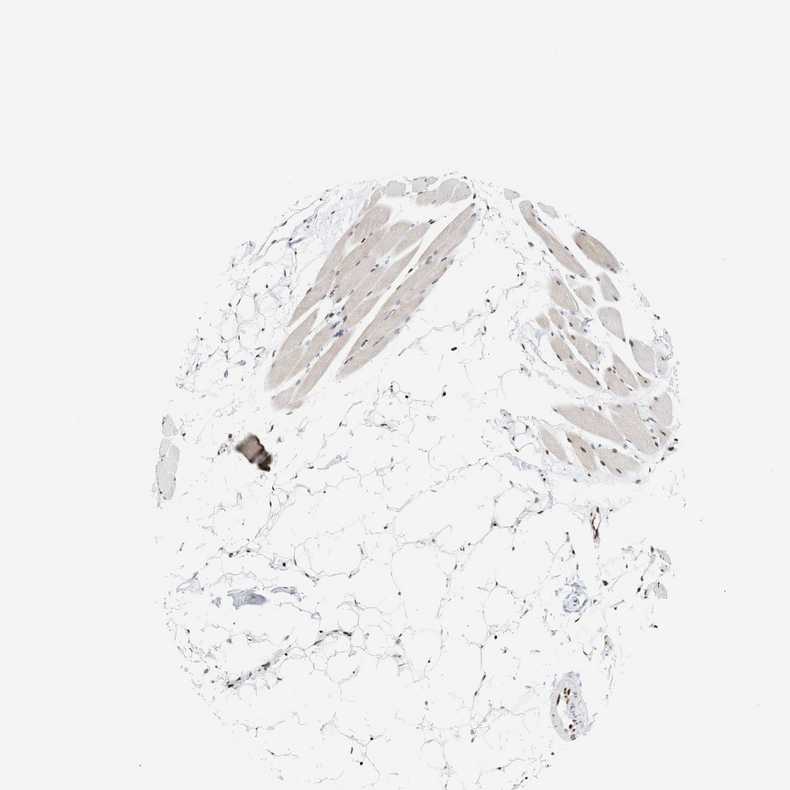

SKELETAL MUSCLE - Antibody stainingi

Antibody staining in the annotated cell types in the current human tissue is reported as not detected, low, medium, or high, based on conventional immunohistochemistry profiling in selected tissues. This score is based on the combination of the staining intensity and fraction of stained cells.

Each image is clickable and will lead to virtual microscopy that enables deeper exploration of all samples and also displays staining intensity scores, fraction scores and subcellular localization as well as patient and tissue information for each sample.

Antibody HPA022961Antibody HPA024457

Myocytes MediumHigh